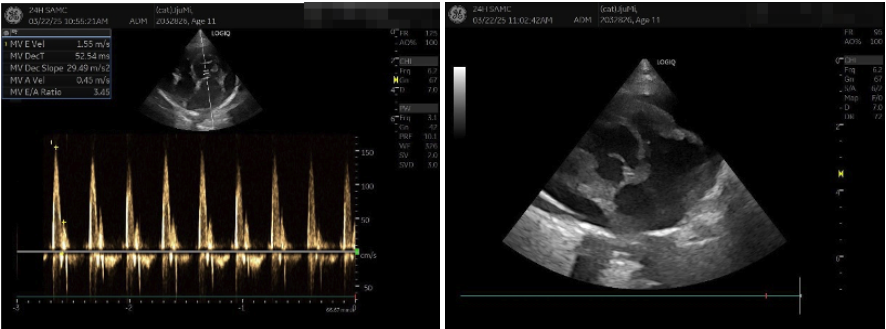

03 심장초음파 검사

즉각적인 호흡개선을 위한 강심제, 이뇨제 등의 응급 약물이 투여와 산소 공급 후 심장초음파 검사가 진행되었습니다.

고양이 제한성심근병증 심장초음파 검사 / 출처: 에스동물메디컬센터 양산점

이번 환자의 경우 심장초음파 검사상 일반적인 비대성심근병증(HCM)과 다르게 심근의 비대가 심각하지 않은 편이었습니다. 그에 비하여 심한 이완 기능장애에 동반된 좌측 심방의 확장이 심한 편으로 제한성심근병증(RCM)에 해당되는 심장초음파 소견이 확인되었습니다.